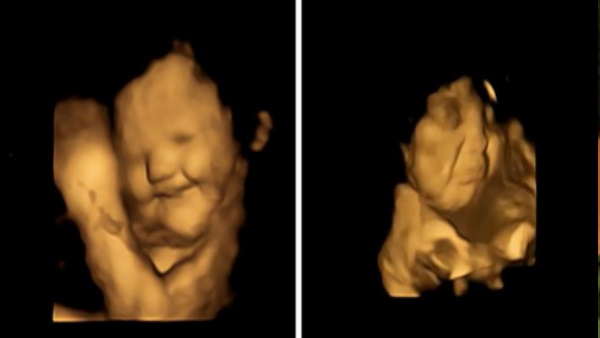

महिलाओं के 4 डी अल्ट्रासाउंड स्कैन में खुला ये राज

ये कैप्सूल खाने के लगभग 20 मिनट बाद महिलाओं के 4 डी अल्ट्रासाउंड स्कैन से पता चला कि अपनी मां द्वारा खाए गए कली के स्वाद के संपर्क में आने पर भ्रूण गर्भ में "रोने वाला चेहरा" बनाते हैं और गाजर के संपर्क में आने पर "हंसता-चेहरा" की प्रतिक्रिया अधिक होती है।